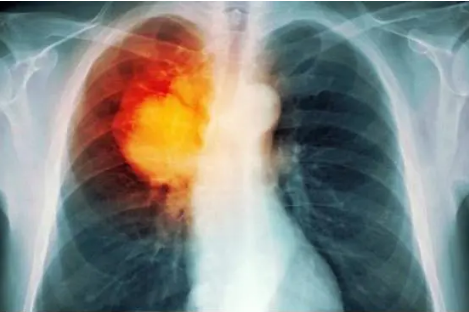

一、吸烟如何摧毁你的肺部?

吸烟就像在给肺部“埋地雷”,每一口烟雾都在一点点侵蚀它的健康,香烟里的7000多种化学物质中,有上百种是已知的致癌物,还有数千种对人体有害的化合物。

一旦吸入这些物质,肺部会立刻承受它们的冲击。

首先,香烟烟雾会直接破坏肺部的纤毛,这些纤毛是肺部的“清洁工”,它们的任务就是将灰尘、细菌和其他杂质从气道扫出去。

但香烟中的有害物质会让这些纤毛变得迟缓甚至停止摆动,无法完成它们的工作,就好比街道的清扫工罢工了,垃圾堆积得越来越多。纤毛的功能一旦受损,吸入的杂质就会越积越深,最终堆积在肺部,形成难以清除的毒素沉积。

香烟中的焦油是肺部的另一个大敌,它会像涂层一样覆盖在肺泡表面,阻碍正常的气体交换过程。简单来说,肺泡是吸收氧气、排出二氧化碳的核心“设备”,可一旦被焦油覆盖,这些肺泡的工作效率会大打折扣。

烟雾中的一氧化碳也是杀手之一,它会直接与血液中的血红蛋白结合,抢占氧气的“座位”。这样一来,身体的各个器官就像被限制供氧一样,开始进入慢性缺氧状态,这会导致肺部加速老化。

长期吸烟还会对肺组织造成结构性的破坏,正常的肺部应该是柔软有弹性的,就像气球一样能够自由膨胀和收缩。但香烟中的化学物质会让肺组织逐渐变硬,肺泡壁开始永久性地破裂,这种破坏无法修复,直接导致慢性阻塞性肺疾病(慢阻肺)的发生,让呼吸变得越来越困难。

健康的肺部是淡红色的,充满生机,而长期吸烟的肺部则会被杂质染成深黑色,甚至伴有硬化的斑块。这个黑色并不是简单的污渍,而是毒素的沉积,证明着肺部已经被烟雾侵蚀得无法自洁。

每一口烟雾吸入体内,都会成为肺部的负担,日积月累就像一场慢性的内部战争。总之,吸烟不仅毁掉肺的健康,还会带走它的生命力,让整个身体陷入危机之中。